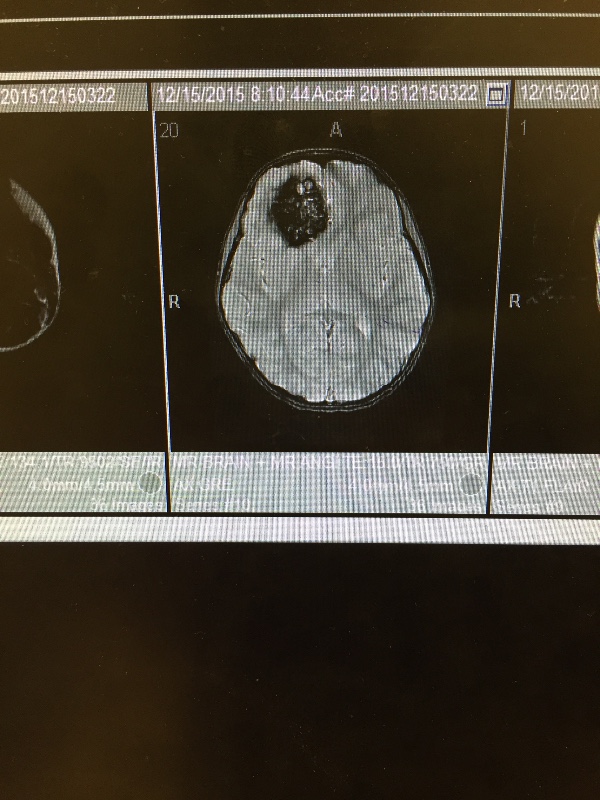

The correct name of what Gianna was diagnosed with is called Familial Cerebral Cavernous Malformation (CCM1). Her MRI results discovered she has four cavernomas. One of the cavernomas measures 2 inches and is located in the frontal lobe of her brain. There is an additional cavernoma pressed up against the 2 inch cavernoma. She has two more cavernomas that are located in areas that are too high of a risk to remove at this time. The Surgeon said because of the size of the large cavernoma if we were to leave it and it were to bleed it would have catastrophic results. It has already bled some which has caused her the Chronic migraines. Gianna’s Neurosurgeon has scheduled her to have surgery to remove the two inch cavenoma and the small one next to it, within the next few weeks. She will need to be in the hospital for about one week, if everything goes well.